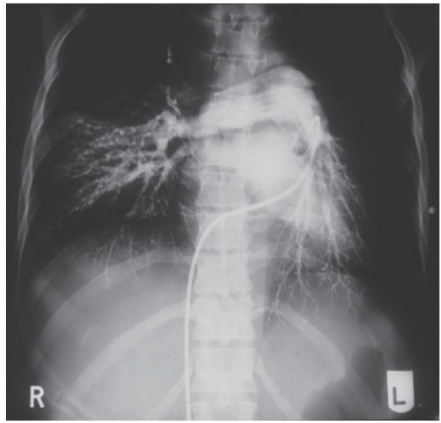

Uma mulher, 32 anos, foi internada devido a uma dispneia

intensa e vertigem ao esforço. Durante a anamnese, ela relata

parto vaginal cerca de 3 meses antes de buscar o pronto-socorro

e retorno recente do uso de anticoncepcionais orais combinados.

Apresenta dor torácica bilateral, sugestiva de caráter pleurítico.

Foi solicitada uma angiotomografia com o resultado a seguir:

Com isso, o diagnóstico mais provável é: